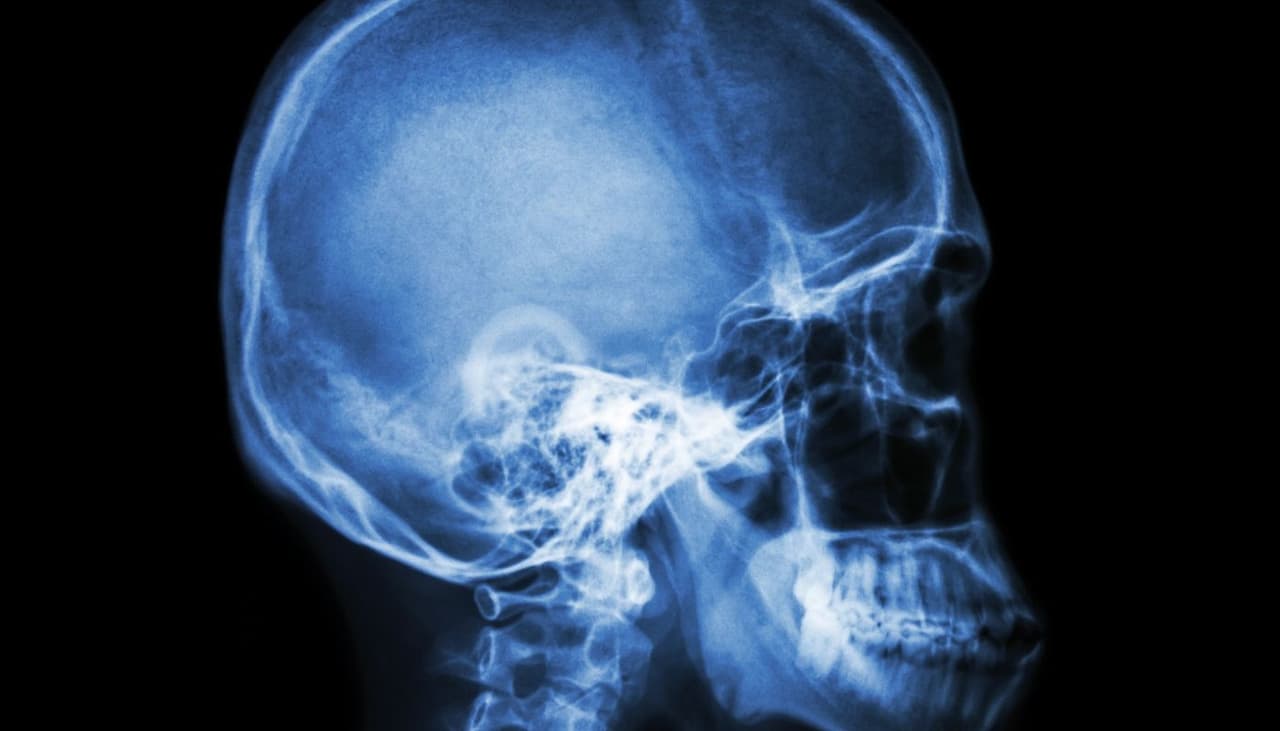

Como todo el mundo sabe, la osteoporosis es una patología que afecta normalmente a las mujeres. Se trata de una enfermedad crónica que reduce la masa ósea, haciendo que los huesos sean más frágiles, sometiéndolos a un riesgo de deformación y provocando un fuerte dolor diario.

Como todo el mundo sabe, los huesos están formados por tejidos vivos, dicho de otra forma, por estructuras que evolucionan con el tiempo desde el nacimiento, adquiriendo densidad y fuerza a medida que vamos creciendo.

Nuestro crecimiento se efectúa durante la infancia y la adolescencia, hasta la edad de los 20 años, cuando se alcanza el pico más alto de la masa ósea. Todo esto significa que el desarrollo de una persona es esencial para poder adquirir unos huesos más firmes, sanos y resistentes con los años.

Nuestra alimentación y nuestros hábitos de vida son dos factores primordiales puesto que nos permiten adquirir una buena masa ósea. Sin embargo, a veces se sufren carencias de calcio, de flúor o de vitamina D. Esta es la razón por la cual vamos a analizar los factores que determinan la aparición de la osteoporosis.